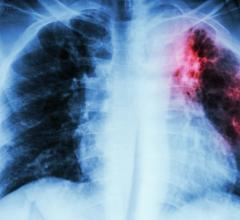

“Lung cancer is the deadliest cancer in men and in women, and it all boils down to how it is detected and when it is ...